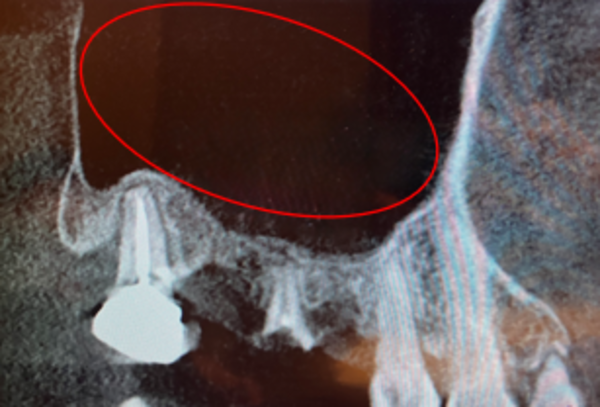

なお、抜歯前に撮影したCT画像では、副鼻腔内膜が歯由来の感染症で炎症を起こし、かなり肥厚しているのが確認されたのですが、サイナスリフト前に再度CTを撮影したところ、肥厚は消失し綺麗になっているのが確認できました。

白っぽく膨らんで見える部分が肥厚です。抜歯後には感染が除去されたことにより肥厚が綺麗になくなっていました。

サイナスリフトを行った後、約6ヶ月ほど待ち、再度CTで骨の状態を確認したところ、十分な骨形成が認められました。